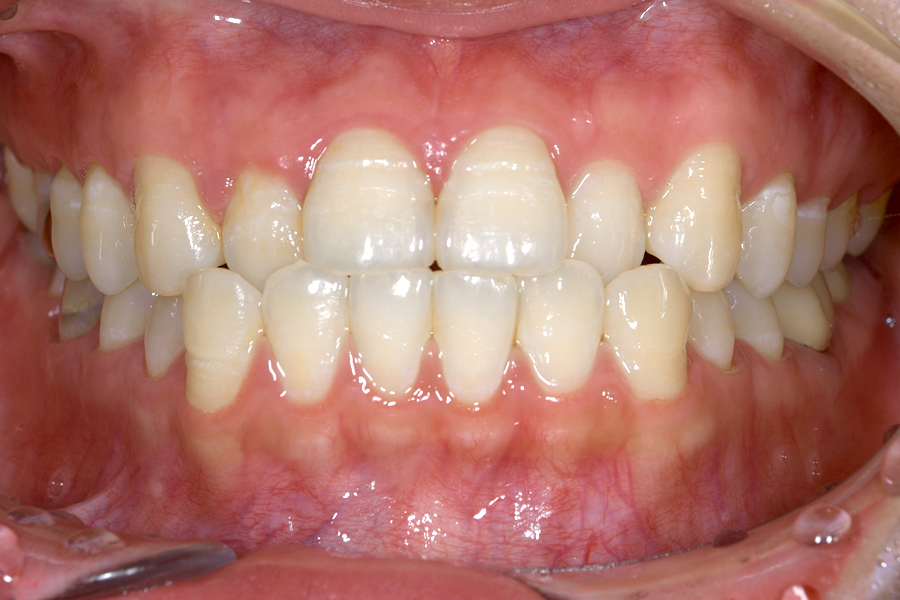

| 主訴 | 上下前歯のガタツキ、かみ合わせが悪い |

| 治療期間 | 2年3か月 |

| 治療費 | マウスピース矯正とホワイトニングセット 1,018,296円(税込) |

| 治療内容 | 目立ちにくいマウスピース矯正(非抜歯矯正) 歯と歯の間に隙間をつくることにより、歯列弓を広げながら治療を行いました。 また矯正用マウスピースをトレー代わりにし、ジェルを入れてホームホワイトニングを同時に行っております。 |

| 治療のリスク |

・後戻りする可能性があるのでリテーナーを最低でも矯正期間以上はつけること。 ・ホワイトニング後、一時的に痛みが出る場合があります。 ・稀にほっぺた、唇、舌などに口内炎や傷ができることがあります。 |